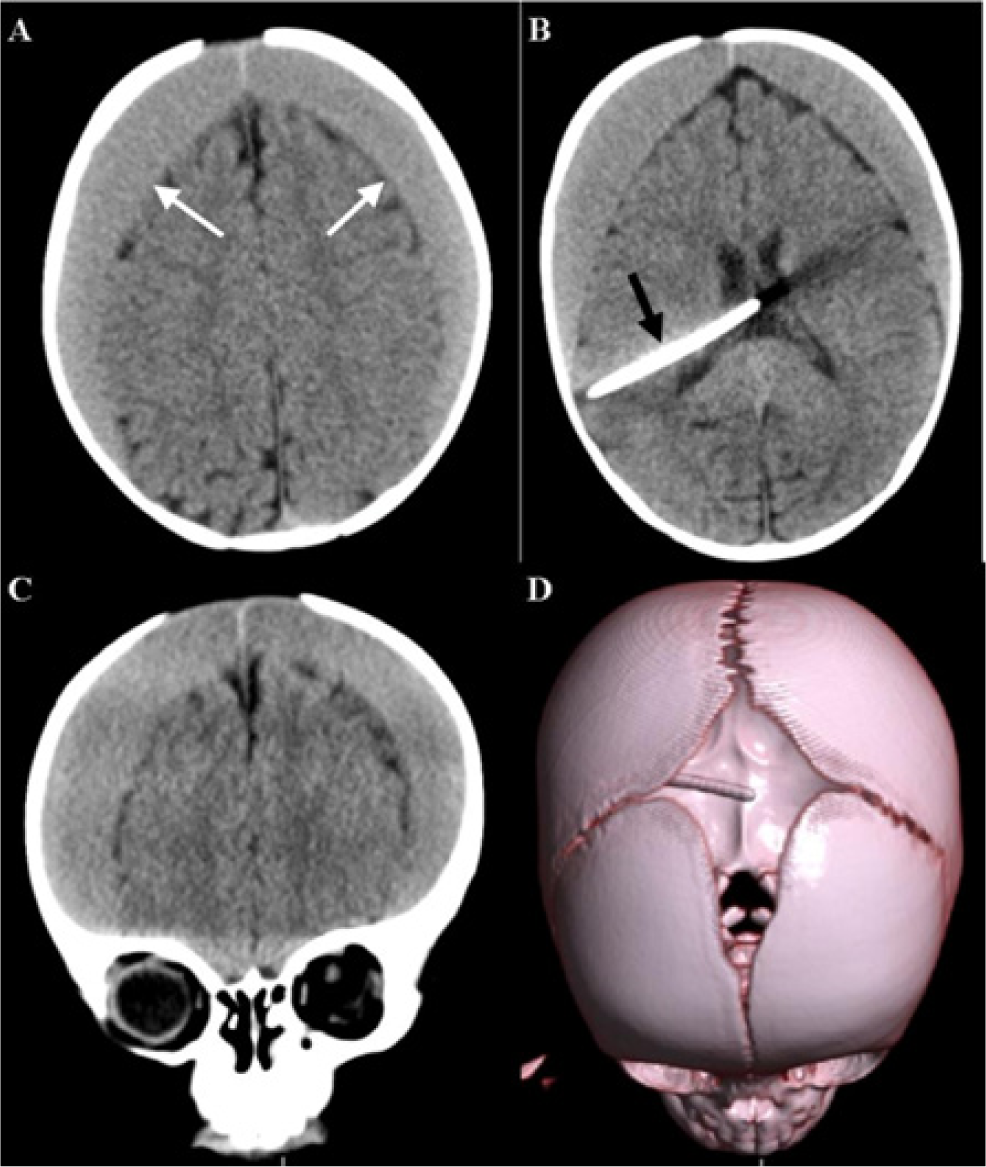

There is an unmet need for the treatment of hydrocephalus in Tanzania. Thousands of newborns each year in the region are affected by this condition and access to care remains a challenge. While treatment options like cerebrospinal fluid diversion through ventriculo-peritoneal shunting are within the skill set of general surgeons, the potential complications represent an additional challenge. We present a 10-month-old Tanzanian female who developed bilateral-subdural hematomas after insertion of a ventriculoperitoneal shunt.